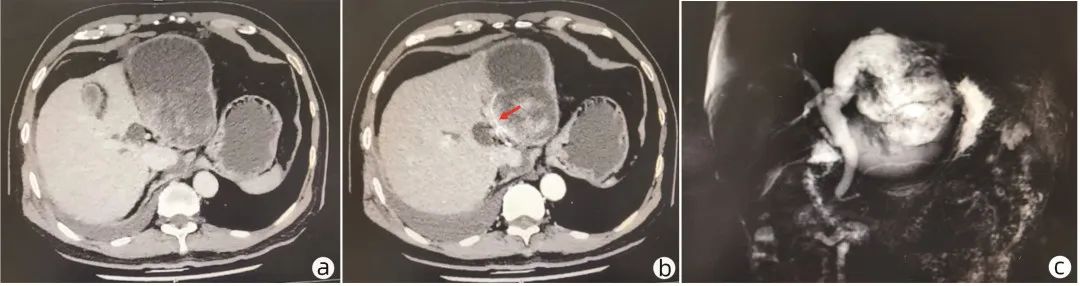

辅助检查:血尿粪常规正常,生化常规、凝血常规正常,甲、乙、戊型病毒性肝炎血清标志物(-),CMV-IgG (+),CMV-IgM (-),T-SPOT(-),TB (-),CRP (-),ESR (-),ANA、ANCA、抗GBM抗体、AIH抗体谱(-)、IgG4(-),CA19-956.8 IU/mL,CEA、AFP、SCC、CA153、CA125、CA724均阴性。心肌酶、BNP正常范围。心电图:窦性心律;心脏彩超:静息状态下超声心动图未见明显异常(无心包积液)。抽腹水呈胶冻样黏液性改变,白细胞3.16×109/L,中性粒细胞4%,淋巴细胞42%,巨噬细胞52%,李凡他(+),白蛋白、葡萄糖、肿瘤指标标本凝固不可测,LDH 3.6 U/L,氯59.2 mmol/L,ADA 0.1 U/L;细菌培养(-),抗酸杆菌涂片(-),乳糜试验(-)。胃镜检查:可见胃体前壁小弯侧一巨大黏膜下隆起,考虑外压可能,余无特殊;肠镜检查无特殊。上腹部增强CT提示肝左叶巨大囊实性占位,其内可见分隔,最大层面大小约11.4 cm×9.8 cm,实性成分和分隔可见强化(图1a、b)。上腹部磁共振胰胆管成像(MRCP)提示左肝内胆管明显扩张,最宽处约1.5 cm;远端见囊实性占位,11 cm×8.4 cm大小;肝内外胆管扩张(图1c)。考虑腹腔巨大包块来源于肝脏,且与胆管相通。

图1  患者术前增强CT及MRCP检查

注:a,肝左叶巨大囊实性占位;b,肝左叶占位内见分隔,实性成分及分隔可见强化(箭头所指为囊壁强化);c,左肝内胆管明显扩张,远端见囊实性占位。